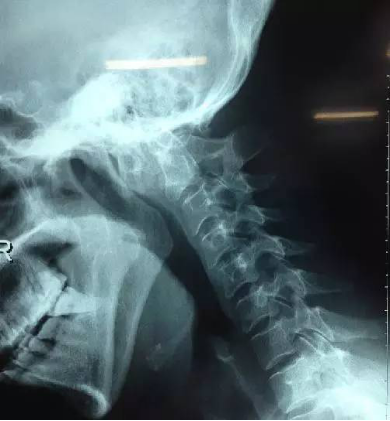

8术后片子

全麻后,显微镜下行颈后路减压+枕颈撑开复位椎弓根侧块(左侧枕骨-C2~3,右侧枕骨-C3)螺钉钛棒内固定+植骨融合术。术中C臂下行枕颈撑开复位椎弓根侧块置钉。术后复查见椎管减压后脊髓位置良好,小脑扁桃体下疝改善,寰枢椎脱位复位。患者症状逐渐好转。